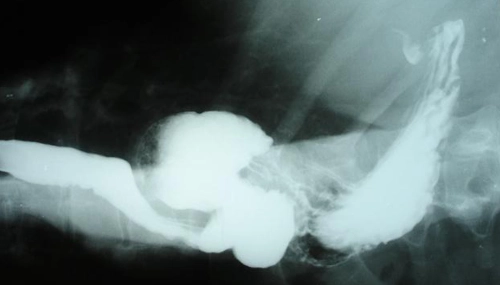

Radiografia mostrando o estômago dentro do tórax (hérnia de hiato grande)